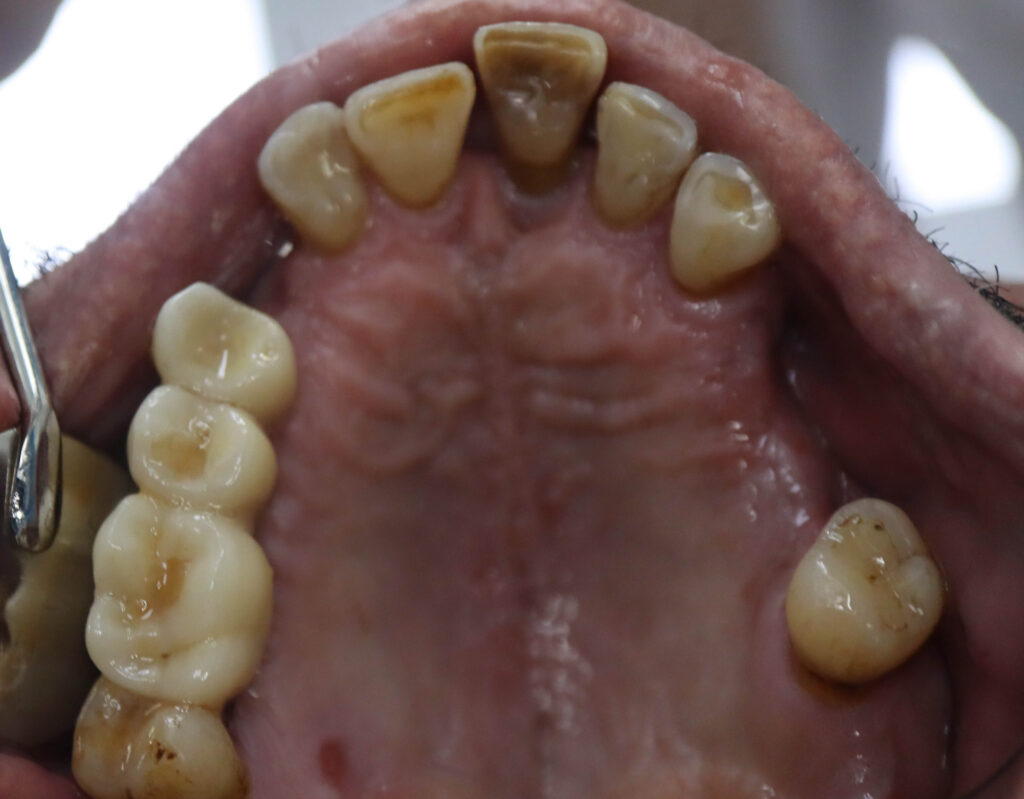

Ситуация до лечения

Пациент обратился с жалобами на эстетические недостатки.

У пациента уже стояло некоторое количество имплантатов. Было решено использовать их при протезировании.

пациент до имплантации